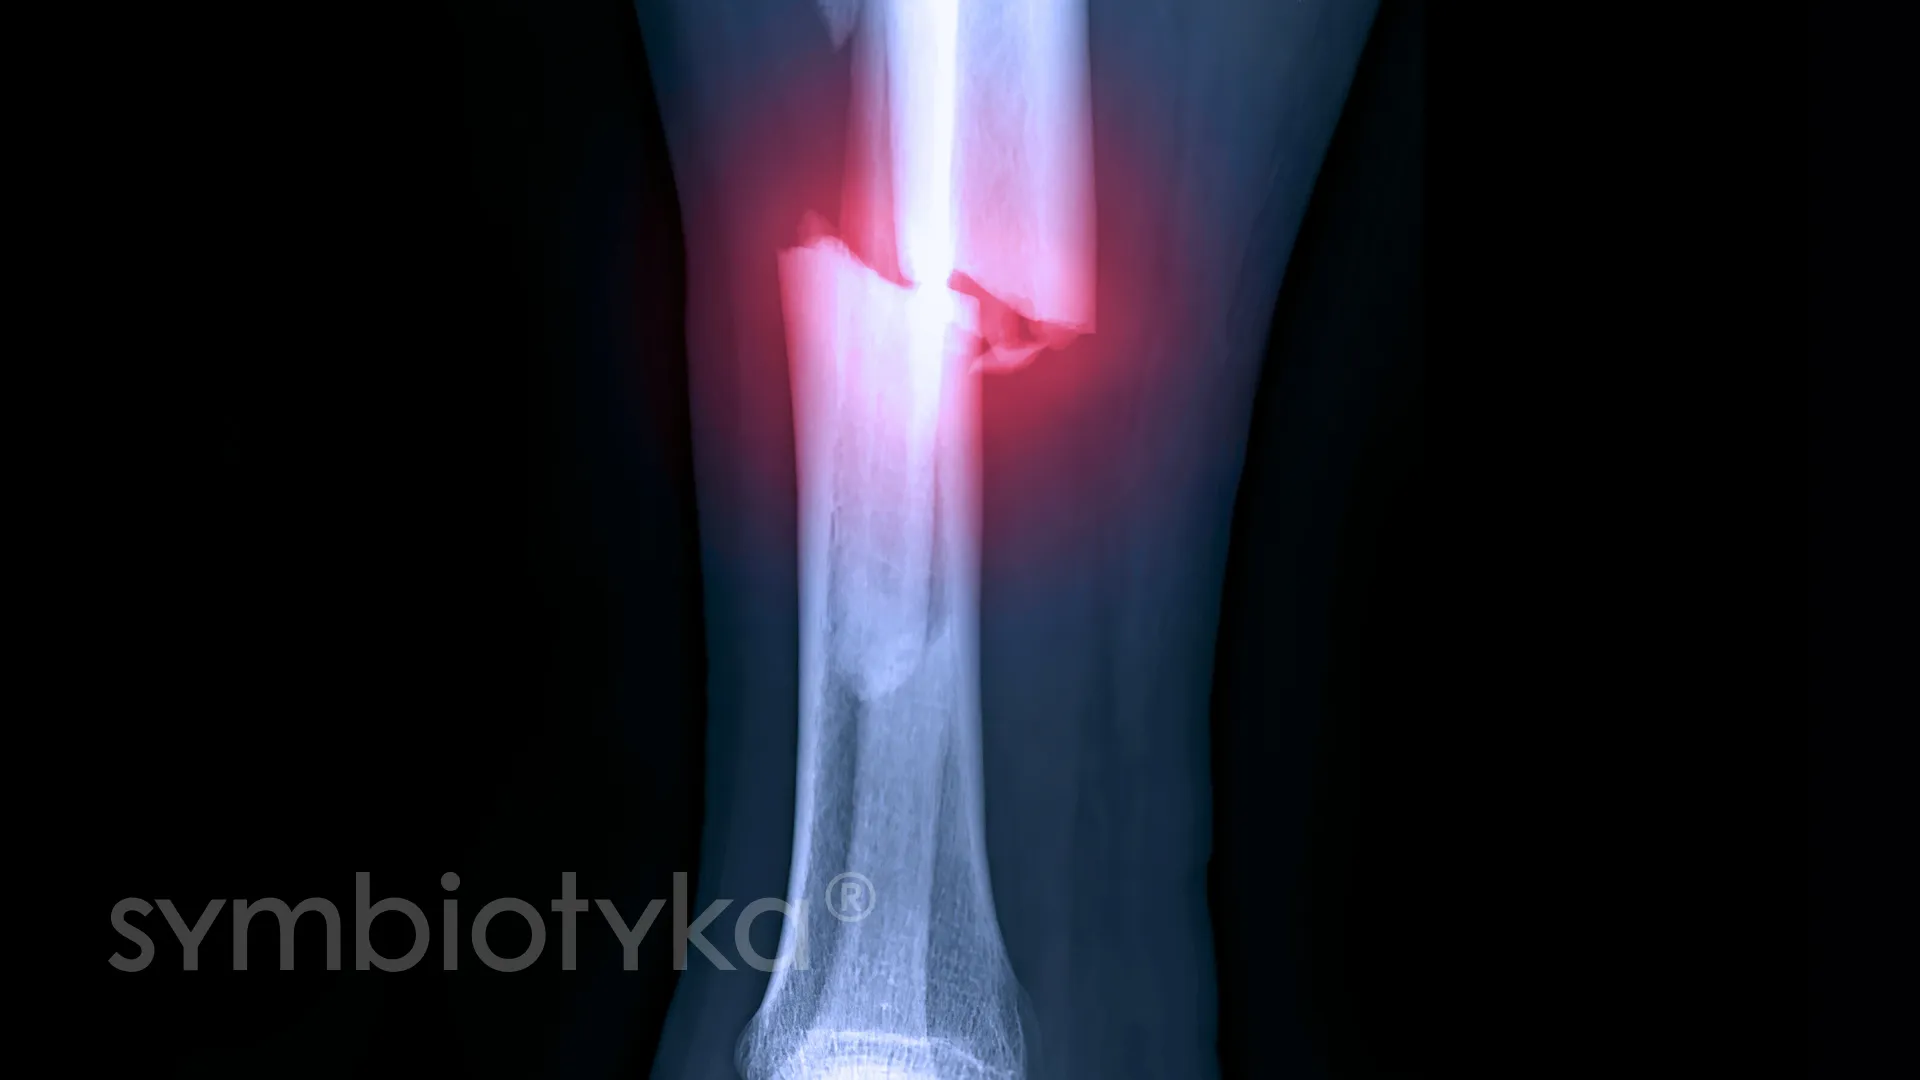

Перелом гомілки може справді налякати, це доволі серйозна травма. Він виникає, коли гомілкова кістка зламана або має тріщину. Що ж, халепа! Але не впадайте в паніку — сучасна медицина на висоті.

Як це діагностують лікарі

Лікарі першими згадують про рентген. Далі можливі магнітно-резонансна томографія або комп’ютерна томографія для уточнення картини.